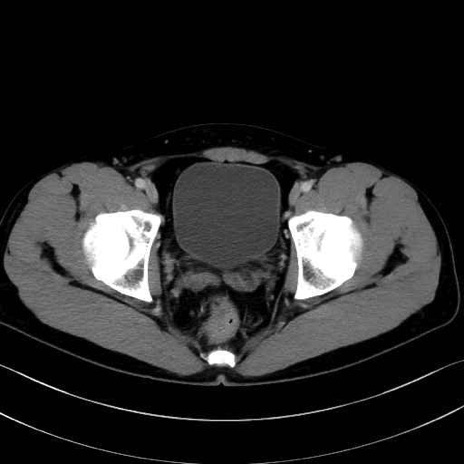

肛門挙筋(levator ani muscle)のCT画像の解剖

肛門挙筋 (Levator ani)